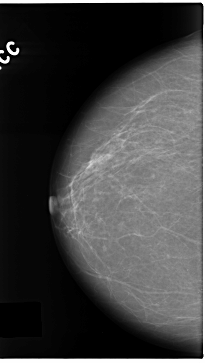

C_0138_1.LEFT_CC

RIGHT_CC LINES 4712 PIXELS_PER_LINE 2656 BITS_PER_PIXEL 12 RESOLUTION 50 NON_OVERLAY